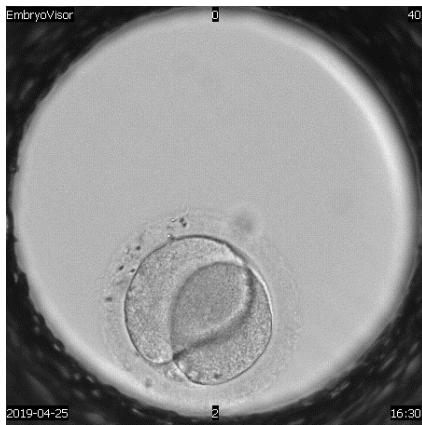

The embryological stage of ART programs is one of the most important, since the assessment of the quality of oocytes, their fertilization and in vitro cultivation to the stage of preimplantation embryos largely determines its success. Morphological evaluation of embryos is the main method of embryo selection. Time-lapse microscopy is one of the modern methods of selecting a high-quality embryo for transfer. In the analysis of many retrospective and prospective studies, they emphasize the advantage and lack of differences compared to traditional morphological assessment of the quality of embryos Almost all publications devoted to timelapse microscopy have focused on determining the timing of specific events of embryo division and then using this information to create algorithms that help to select embryo for transfer.

A detailed view of techniques used to assess human embryo development to enhance reproductive potential.